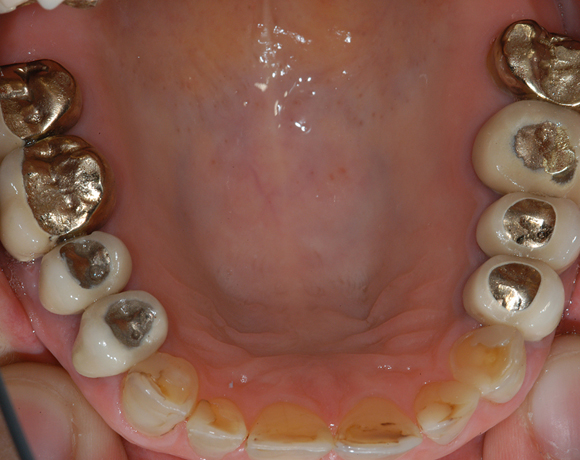

22 Einzelkronen mit Eris for E II

Empress II Presskeramik mit Eris Verblendkeramik bei einer Neuversorgung im Oberkiefer komplett und im Unterkiefer Vollkronen auf den Seitenzähnen.

Ein Projekt aus dem Jahr 2004

Hier wurden der ganze Oberkiefer und die Seitenzähne im Unterkiefer mit neuen Kronen aus Empress 2 und mit Eris Verblendkeramik versorgt.